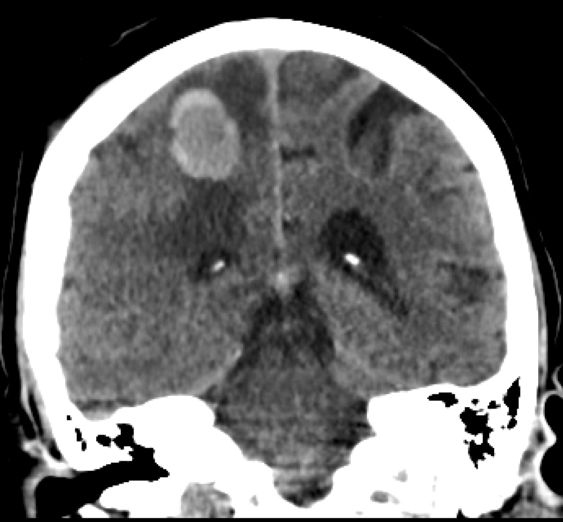

| Gehirn | Ein Jahr später wurde die Patientin krampfend und kollaptisch in der Wohnung aufgefunden. Ein CT ergab eine Hirnmetastase, die neurochirurgisch entfernt werden konnte.![]() |

![]() | |